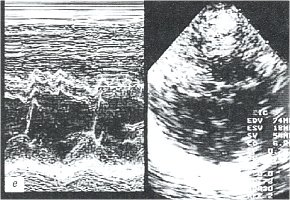

При эхокардиографическом (ЭХОКГ) исследовании выявлены гиперэхогенные включения на внутренних поверхностях листков перикарда, отсутствие эхонегативного пространства за передней стенкой правого желудочка, за задней стенкой левого желудочка и верхушкой; параллельное переднезаднее движение листков перикарда; нарушение диастолической функции миокарда левого желудочка (рис. 1в, г).

в) Эхокардиограмма.

г) Эхокардиограмма.